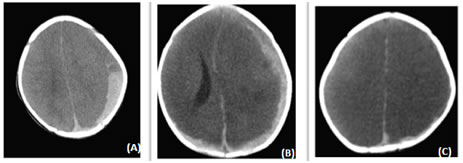

Figure 8: Axial NECT scan a) A 6 month old presented after history of fall Concavo-convex shaped sub-acute SDH in left fronto-parietal location, b) SDH along the left fronto-parietal convexity and right parietal convexity in a 1 month old male infant. c) SDH along the left high parietal convexity in a 6 month old female child.